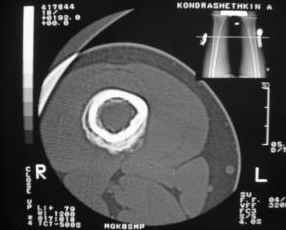

Анамнез практически никакой: в следствие травмы (растяжение связок коленного сустава) от 07.11.2004 выполнены Rg-граммы в травмпункте и обнаружено опухолевидное образование. Первичные Rg-граммы я не публикую, так как они заметно худшего качества, да и динамики за прошедшие три недели не отражают. Болевой синдром купирован в течение трёх дней. В настоящий момент мальчика ничего не беспокоит. Ходьба не нарушена, опухоль пальпируется с трудом по задней поверхности в н\3 правого бедра, пальпация безболезненна, объем движений в суставах правой нижней конечности полный и симметричный. Кожа над опухолью не изменена. В нашей клинике проведено дополнительное обследование: общие анализы крови и мочи, биохимия крови без особенностей. Выполнены Rg-граммы на цифровом Siemens обычные и продольные томограммы срезами 3-5 мм, а также компьютерная томография поперечными срезами по 5 мм. Прошу обратить внимание, что на приведённых томограммах видны две полости 10х15 мм и 15х60 мм. Также имеются два опухолевидных образований наслаивающихся друг на друга: уплощённое и вытянутое 10х100 мм и элипсовидной формы 15х30 мм. Это хорошо заметно на фото a_1.jpg c_1.jpg и d_1.jpg. Плотность внутри полостей 125% от плотности костномозгового канала, плотность наружного опухолевидного образования 55% от плотности кортикального слоя. Также отмечается линия перелома по центру наружного опухолевидного образования. Исходя из полученных данных мнения в плане диагноза несколько разделились от 1)сочетания кортикальной фиброзной дисплазии и латентно протекавшего маршевого перелома н\3 правого бедра до 2)остеосаркомы. В отношении первого варианта не сходится отсутствие клиники при переломе такой крупной кости как бедро, второй вариант вообще оставлю без комментария, ибо некомпетентен. Хотелось бы услышать мнения коллег, с удовольствием ознакомлюсь с любыми предположениями и замечаниями. С уважением, Александр Е. Клоков Отделение детской ортопедии и травматологии БСМП г. Мурманска.